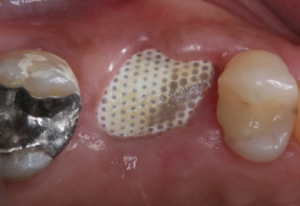

Vista oclusal do alvéolo preenchido pelo enxerto Extra Graft e membrana em posição.

Vista oclusal do alvéolo selado pela membrana Cytoplast .